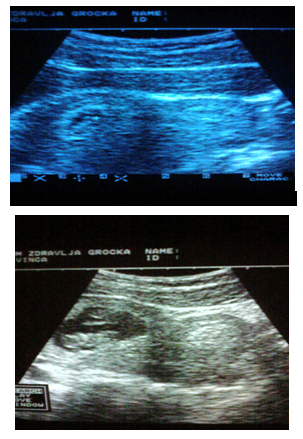

Figure 2 Patient Dj.B.1983 age. Ultrasound examination carried out 5 times. Spontaneously delivered a live male child 2600/50.